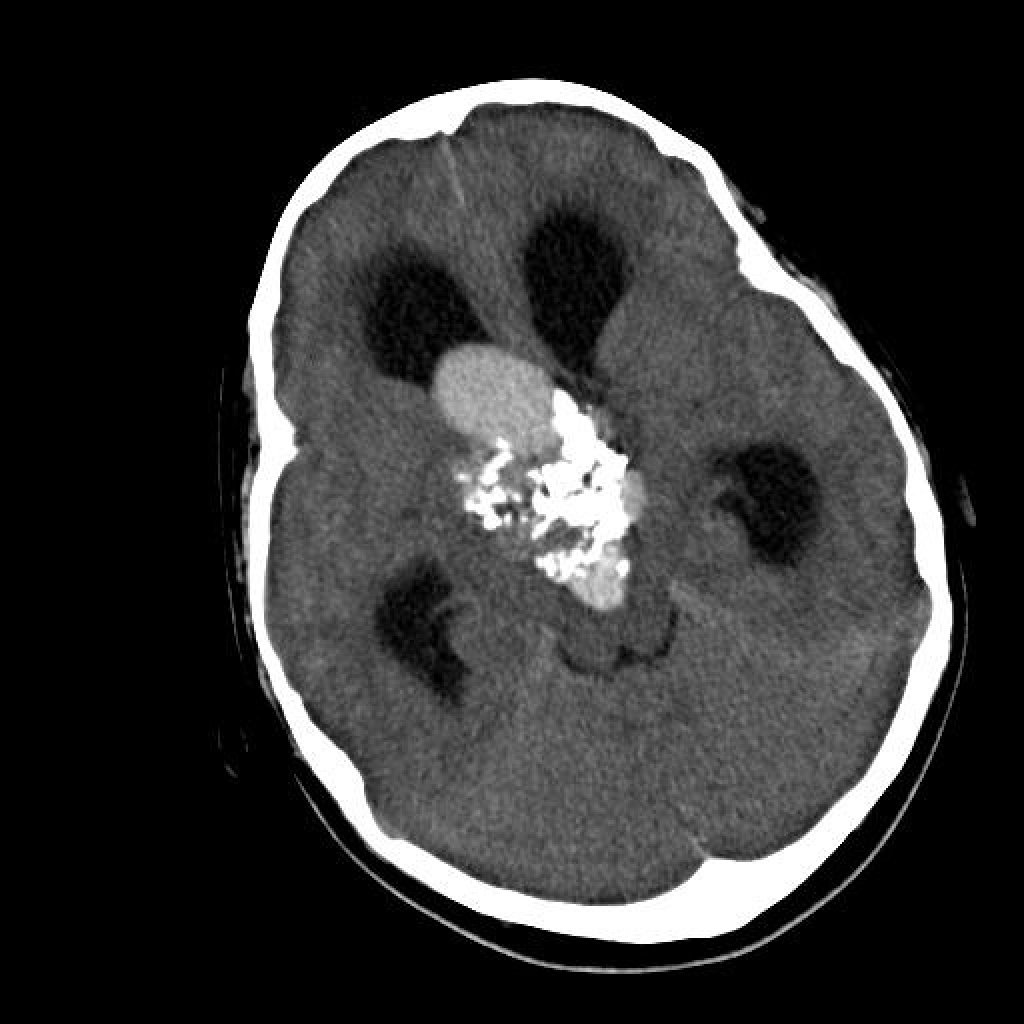

- Компьютерная томография (КТ). КТ незаменима для оценки костных структур основания черепа. Она показывает, есть ли разрушение кости опухолью, и помогает хирургу спланировать костную часть доступа. КТ-ангиография используется для детального изучения сосудов.

Все эти данные загружаются в специальную навигационную станцию. Это позволяет создать трехмерную модель головы пациента, на которой хирург может виртуально спланировать ход операции, выбрав самый безопасный путь к патологии. Такая технология, называемая нейронавигацией, работает как GPS-система во время самого вмешательства, повышая его точность.